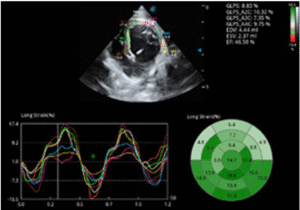

• Cardiology

Echocardiography remains one of the gold standards for diagnosing and monitoring heart disease, including cardiomyopathies, valvular disease, and pericardial effusion.

▸ Heart murmur or respiratory distress

→ Echocardiography to assess cardiac structure and function before initiating treatment